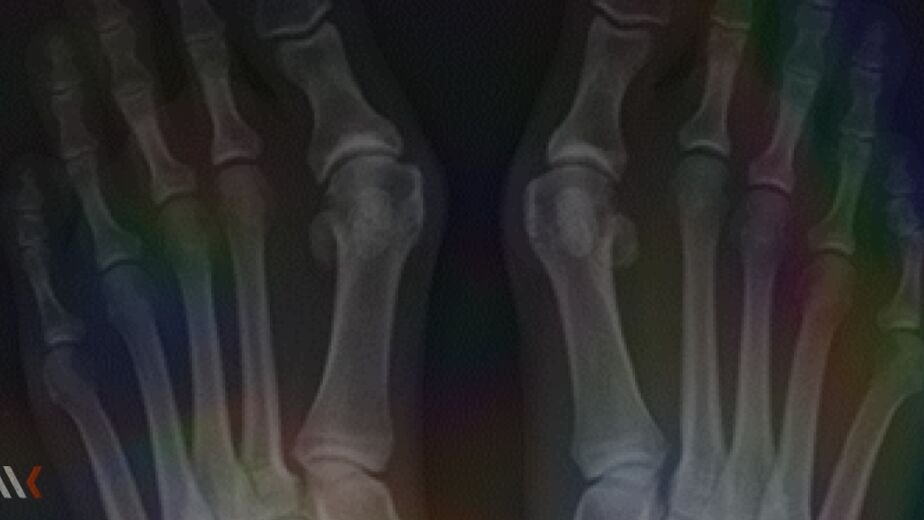

One of the most common foot health problems in adults is hallux valgus. The primary goal of hallux valgus…